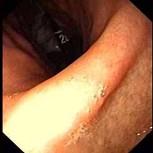

问题 女,36岁,上腹痛2年,伴嗳气、呃逆,弯腰时加重,查体未见特殊。胃镜如图,钡餐未:可见左侧隔上囊状阴影。最可能的诊断是 ( )

选项 A.食管裂孔疝 B.胆石症 C.消化性溃疡 D.幽门梗阻 E.反流性食管炎

答案 A